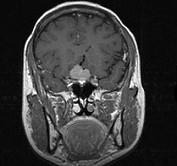

问题 女,32岁,右眼视物模糊1年,加重2月,请根据所提供图像,选择最可能的诊断()

选项 A.鞍区脑膜瘤 B.鞍区垂体瘤 C.鞍区转移瘤 D.鞍区海绵状血管瘤 E.鞍区动脉瘤

答案 A